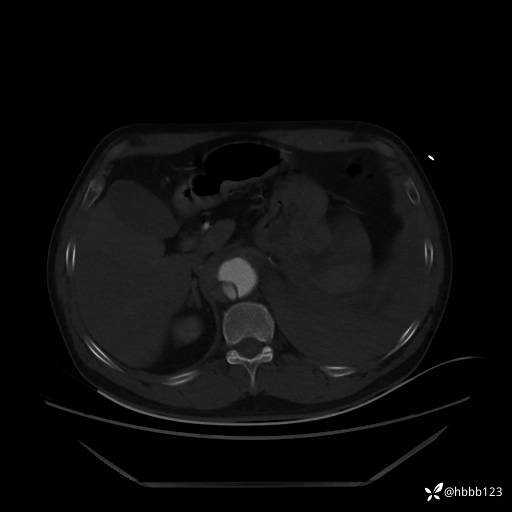

急查胸腹主动脉CTA:

(为方便观察,调至骨窗)